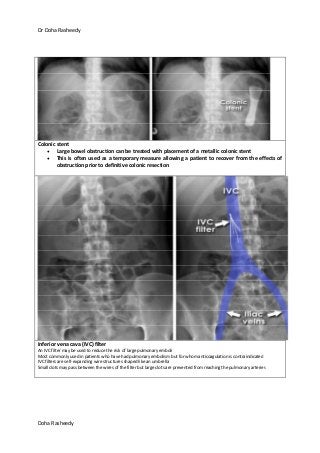

Colonic stent

Large bowel obstruction can be treated with placement of a metallic colonic stent

This is often used as a temporary measure allowing a patient to recover from the effects of

obstruction prior to definitive colonic resection

Inferior vena cava (IVC) filter

An IVC filter may be used to reduce the risk of large pulmonary emboli

Most commonly used in patients who have had pulmonary embolism but for whom anticoagulation is contraindicated

IVC filters are self-expanding wire structures shaped like an umbrella

Small clots may pass between the wires of the filter but large clots are prevented from reaching the pulmonary arteries